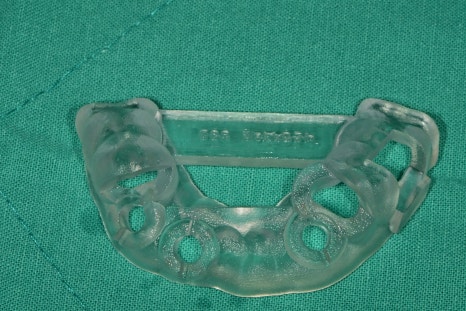

제가 설계한 임플란트 식립 방향을 피드백을 주며

제작센터에서 가이드가 제작이 되어 왔습니다.

주변 치아에 기준점을 두고 제작이 되어 오차가 최소화가 되었고

임플란트 식립을 위해 경로도 준비가 되어있습니다.